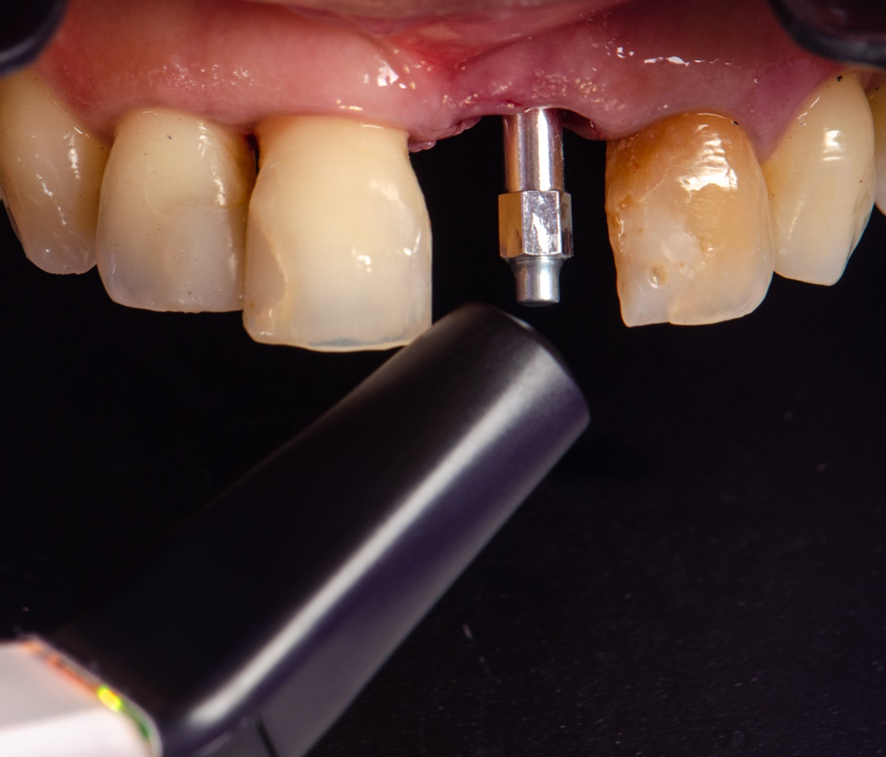

Após o implante instalado, a guia é então removida, e um SmartPeg é fixado sobre a plataforma do implante.

O Osstell é então posicionado sobre o SmartPeg, e os valores de ISQ foram obtidos atraves da RFA, sendo 64 no sentido Vestibulo-Palatino e 65 no sentido Mesio-distal. Isso fez com que optássemos por um cicatrizador personallizado, potencializando assim, um resultado mais previsível.